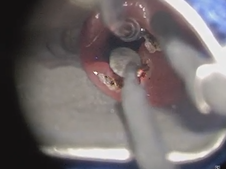

Microdirect Laryngoscopy and CO2 Laser Total Vestibulectomy for Pyolaryngocele

Microdirect Laryngoscopy with CO2 Laser Wedge Excisions for Subglottic Stenosis